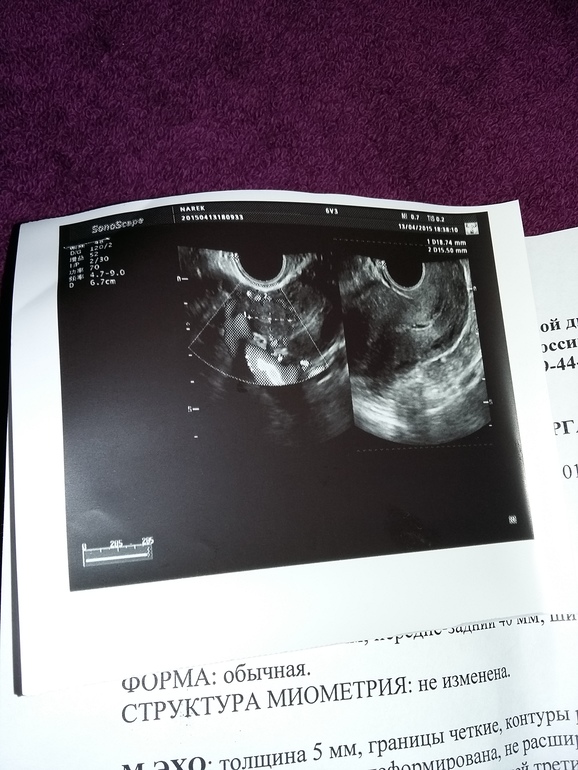

и еще...а вот узи(((

Воть...может таки узистка что-то не то увидела...или у меня сбой, а не ВБ. Ведь до 27 марта, а может и 4 апреля, ну ни как я забеременеть не могла((